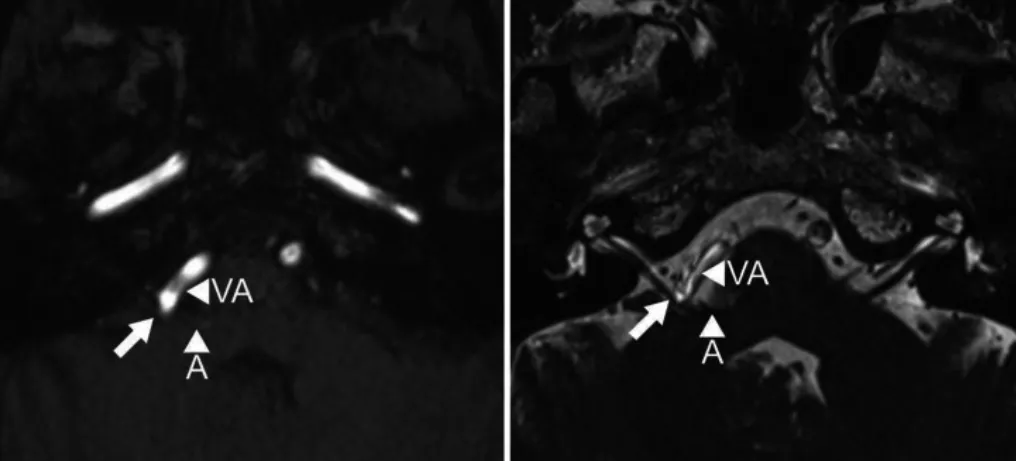

59岁女性,患有进行性右侧面肌痉挛2年。她曾尝试肉毒毒素治疗,但对效果不满意。MRI图像清晰显示小脑前下动脉(AICA)和椎动脉(VA)襻压迫面神经根出脑干区(图1)。

图1,术前MR成像,飞行时间法(左)和稳态构成干涉序列(右)轴位图像显示小脑前下动脉(A)和椎动脉(VA)襻压迫面神经根出脑干区(箭头)。